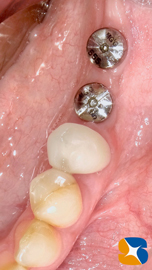

グラグラ動いていたインプラントは、少し引っ張ると簡単に抜けてしまいました。

残された奥のインプラントも方向(角度)が悪いため操作性が良くありません。新しく移植するインプラントとも相性が悪いため、ためらうことなく撤去いたしました。(※事前に説明済み)

簡単に抜け落ちたインプラント跡と残されたインプラント

私の方で新たに2本インプラントの移植および失われた骨の造成も同時に行いました。